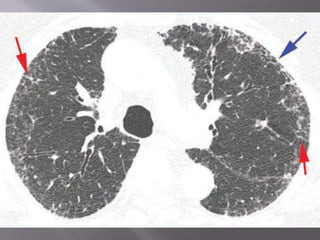

 Early stage - Bilateral irregular linear opacities

causing a reticular pattern , involving lower lung

zone.

 In end stage- extensive honeycombing.

1. Marked fibrosis- On HRCT, IPF is characterized by

intralobular interstitial thickening , results in

reticular pattern in subpleural region - typical

pathological feature of UIP. Dilated and distorted

centrilobular bronchioles are frequently visible

within the areas of reticulation, i.e., traction

bronchiolectasis.

2. Honeycombing- Honeycombing is critical for

making a definitive diagnosis on HRCT,

individual lobules are no longer visible.

Honeycomb cysts usually range from 3 to 10

mm in diameter, but they can be as large as 2.5

cm. The frequency of honeycombing varies

with the severity or stage of the disease.

Findings of honeycombing and fibrosis are

most often symmetric.

3. Patchy involvement- Areas of mild and severe

fibrosis and normal lung are often present in

the same patient, in the same lung, and in the

same lobe.

 A confident diagnosis of IPF on HRCT requires clinical

exclusion of known causes of UIP and the presence of all of

the following four criteria: reticular pattern, honeycombing,

subpleural and basal predominance, and absence of atypical

features.